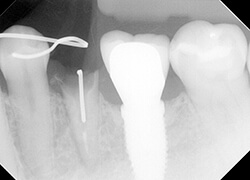

【治療後】

無事挺出が完了しました。骨のレベルから5mm程度の歯根があるのが分かります。

これならファイバーでコアを築造しても、横揺れに強い、つまり折れにくい最終補綴物を入れることが出来ます。